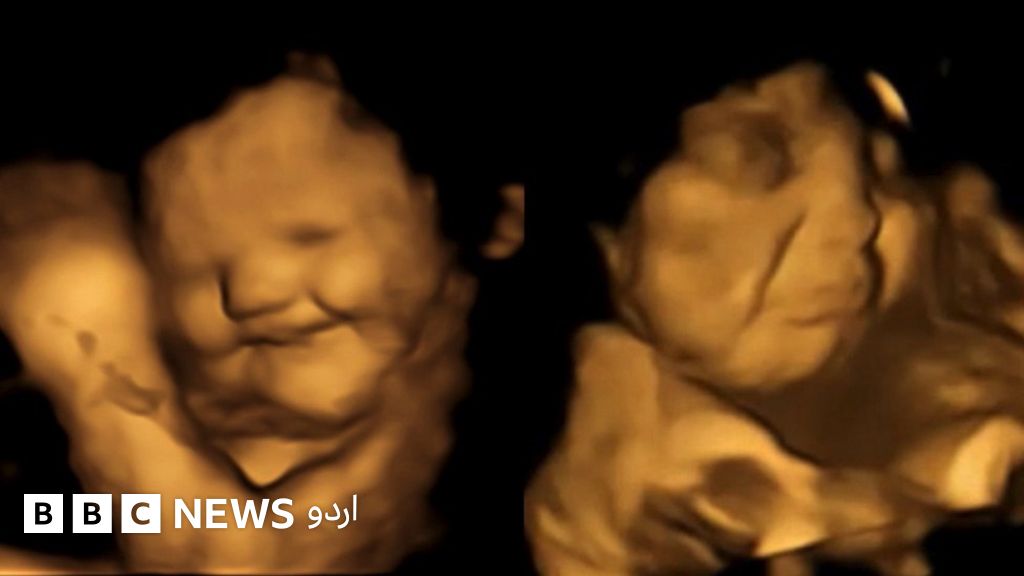

اگر آپ کو گوبھی کا ذائقہ پسند نہیں، تو آپ اکیلے نہیں ہیں۔ سائنسدانوں نے دریافت کیا ہے کہ رحم میں موجود بچے ماؤں کے گاجر کھانے کے بعد مسکراتے ہوئے دکھائی دیتے ہیں اور اگر ماؤں نے گوبھی کھا لی تو وہ تیوریاں چڑھاتے نظر آئے۔

سائیکولوجیکل سائنس کے جریدے میں شائع ہونے والی اس تحقیق میں گروپ نے بتایا کہ ماؤں کے گوبھی والے کیپسول نگلنے کے 20 منٹ بعد، فور ڈی الٹراساؤنڈ سکین سے پتہ چلتا ہے کہ گوبھی کھانے کے بعد زیادہ تر بچوں کے چہرے بگڑنے شروع ہو گئے۔

اس دوران گاجر کے کیپسول کھانے والی ماؤں کے بچے مسکراتے دکھائی دیے۔